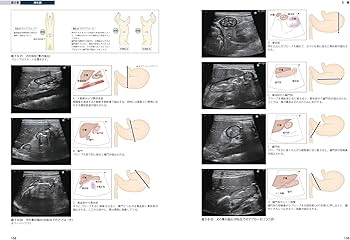

犬と猫の基本的な画像診断に関する専門書。- タイトル: 犬と猫のベーシック画像診断学- ISBN: 978-48931-368-7- 内容: 犬と猫の基本的な画像診断に関する専門書ご覧いただきありがとうございます。卒業が近いので出品させていただきます。ほとんど使用しておりません#獣医